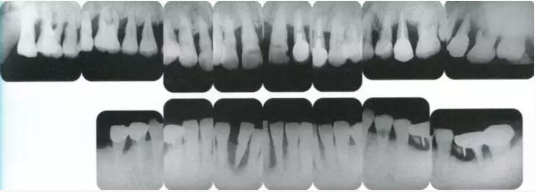

22222222222222222222222222.png

▲圖19-4

X光片。牙槽骨明顯缺失。